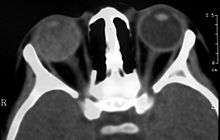

Imaging studies such as ultrasonography (US), Computerized Tomography (CT) and Magnetic Resonance Imaging (MRI) can aid diagnosis. On ultrasound, Coats' disease appears as a hyperechoic mass in the posterior vitreous without posterior acoustic shadowing; vitreous and subretinal hemorrhage may often be observed.[6][7]

On CT, the globe appears hyperdense compared to normal vitreous due to the proteinaceous exudate, which may obliterate the vitreous space in advanced disease. The anterior margin of the subretinal exudate enhances with contrast. Since the retina is fixed posteriorly at the optic disc, this enhancement has a V-shaped configuration.[2]